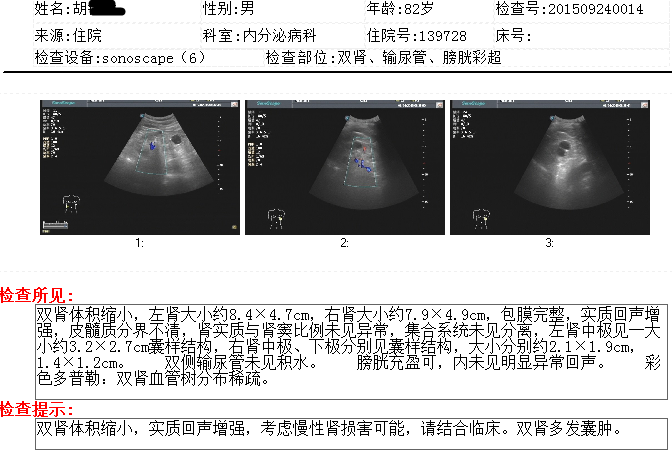

查体:一般状况可。左大腿上部外侧可见一长约15cm手术疤痕。 心肺腹查无明显异常。 脊柱四肢:脊柱呈生理弯曲,无压痛及纵向叩击痛,双手尺偏,双手多个关节屈曲不良右手食、中指间可见痛风石;双下肢凹陷性水肿,无静脉血管曲张。双下肢足背动脉搏动减弱。 神经系统:双膝反射等神经生理性反射正常,巴彬斯基氏征等病理反射未引出。双下肢触痛觉减弱。 辅查:血常规:红细胞总数:RBC 3.30×10^12/L,血红蛋白浓度:HGB 99g/L;尿常规:葡萄糖(GLU): 1+,蛋白(PRO): 3+;大便常规:潜血(免疫法): 阳性(+);肾功能:血肌酐:Cr 319μmol/L,尿素:Urea 16.60mmol/L,β2微球蛋白:B2-MG 13.32mg/L,胱抑素C:Cys-C 3.6mg/L;糖化血红蛋白比值:HbA1c(%) 6.30;24h-尿蛋白定量:24h-U-TP 5355.0mg/24h;内生肌酐清除值:Cr-rate 16mL/min;肝、胆、胰、脾B超: 脂肪肝(轻度)。胆囊附壁结节,考虑息肉可能。双肾、输尿管、膀胱彩超: 双肾体积缩小,实质回声增强,考虑慢性肾损害可能,请结合临床。双肾多发囊肿。肾动脉、肾内小动脉(双侧)彩超: 双侧肾动脉及肾内小动脉血流速度减低,阻力指数增高,请结合临床。心脏彩超(含心功能): 左房大小高值,左室壁稍增厚,左室弛张功能减低,支持高血压性心脏改变。主动脉瓣轻度钙化并轻度返流。二尖瓣、三尖瓣轻度返流。静息状态未见明显节段性室壁运动异常。左室收缩功能正常。心包积液(少量)。请结合临床。双下肢静脉(髂、股、腘、大隐静脉)彩超: 双下肢深静脉主干管腔、血流及瓣膜功能尚可,目前未见明显血栓形成。